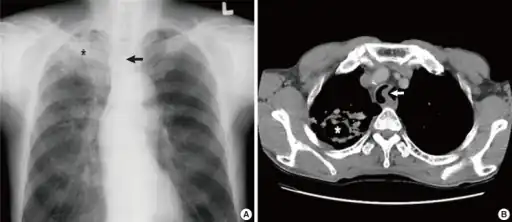

a)Image reveals tuberculosis asterisk b) CT scan of the chest shows tuberculosis with cavitation asterisk -